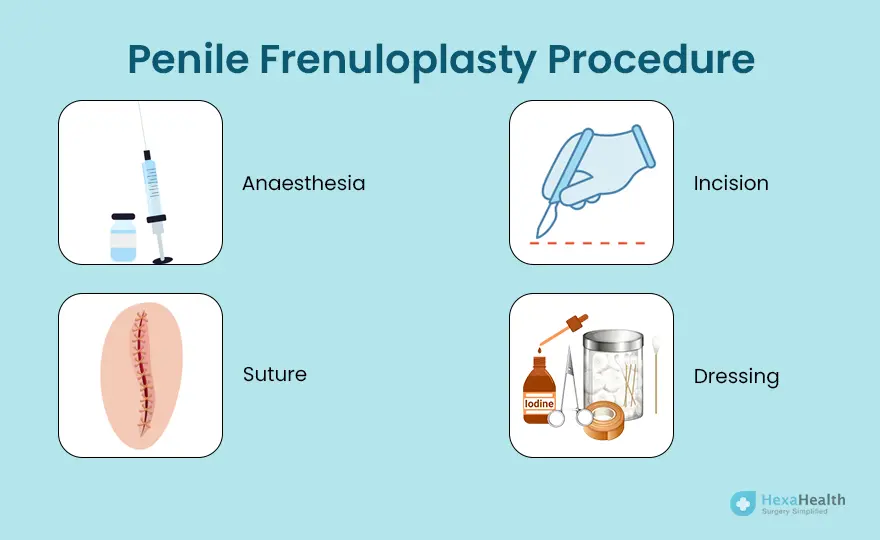

Procedure and Process Treatment

- Local anesthesia before surgery

- Minor incision and reconstruction of frenulum

- Post-op antibiotic and healing care